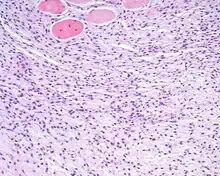

An intermediate power hematoxylin and eosin stained section of an ectomesenchymal chondromyxoid tumor, showing skeletal muscle entrapment. Note the "net-like" appearance (lower portion).

The cells may extend into and entrap soft tissue structures including skeletal muscle and nerve bundles.

• Submucosal unencapsulated but well-delineated or circumscribed nodule, often separated from the periphery and internally by fibrous connective tissue bands. The cells are arranged in cords, nests, and net-like sheets.